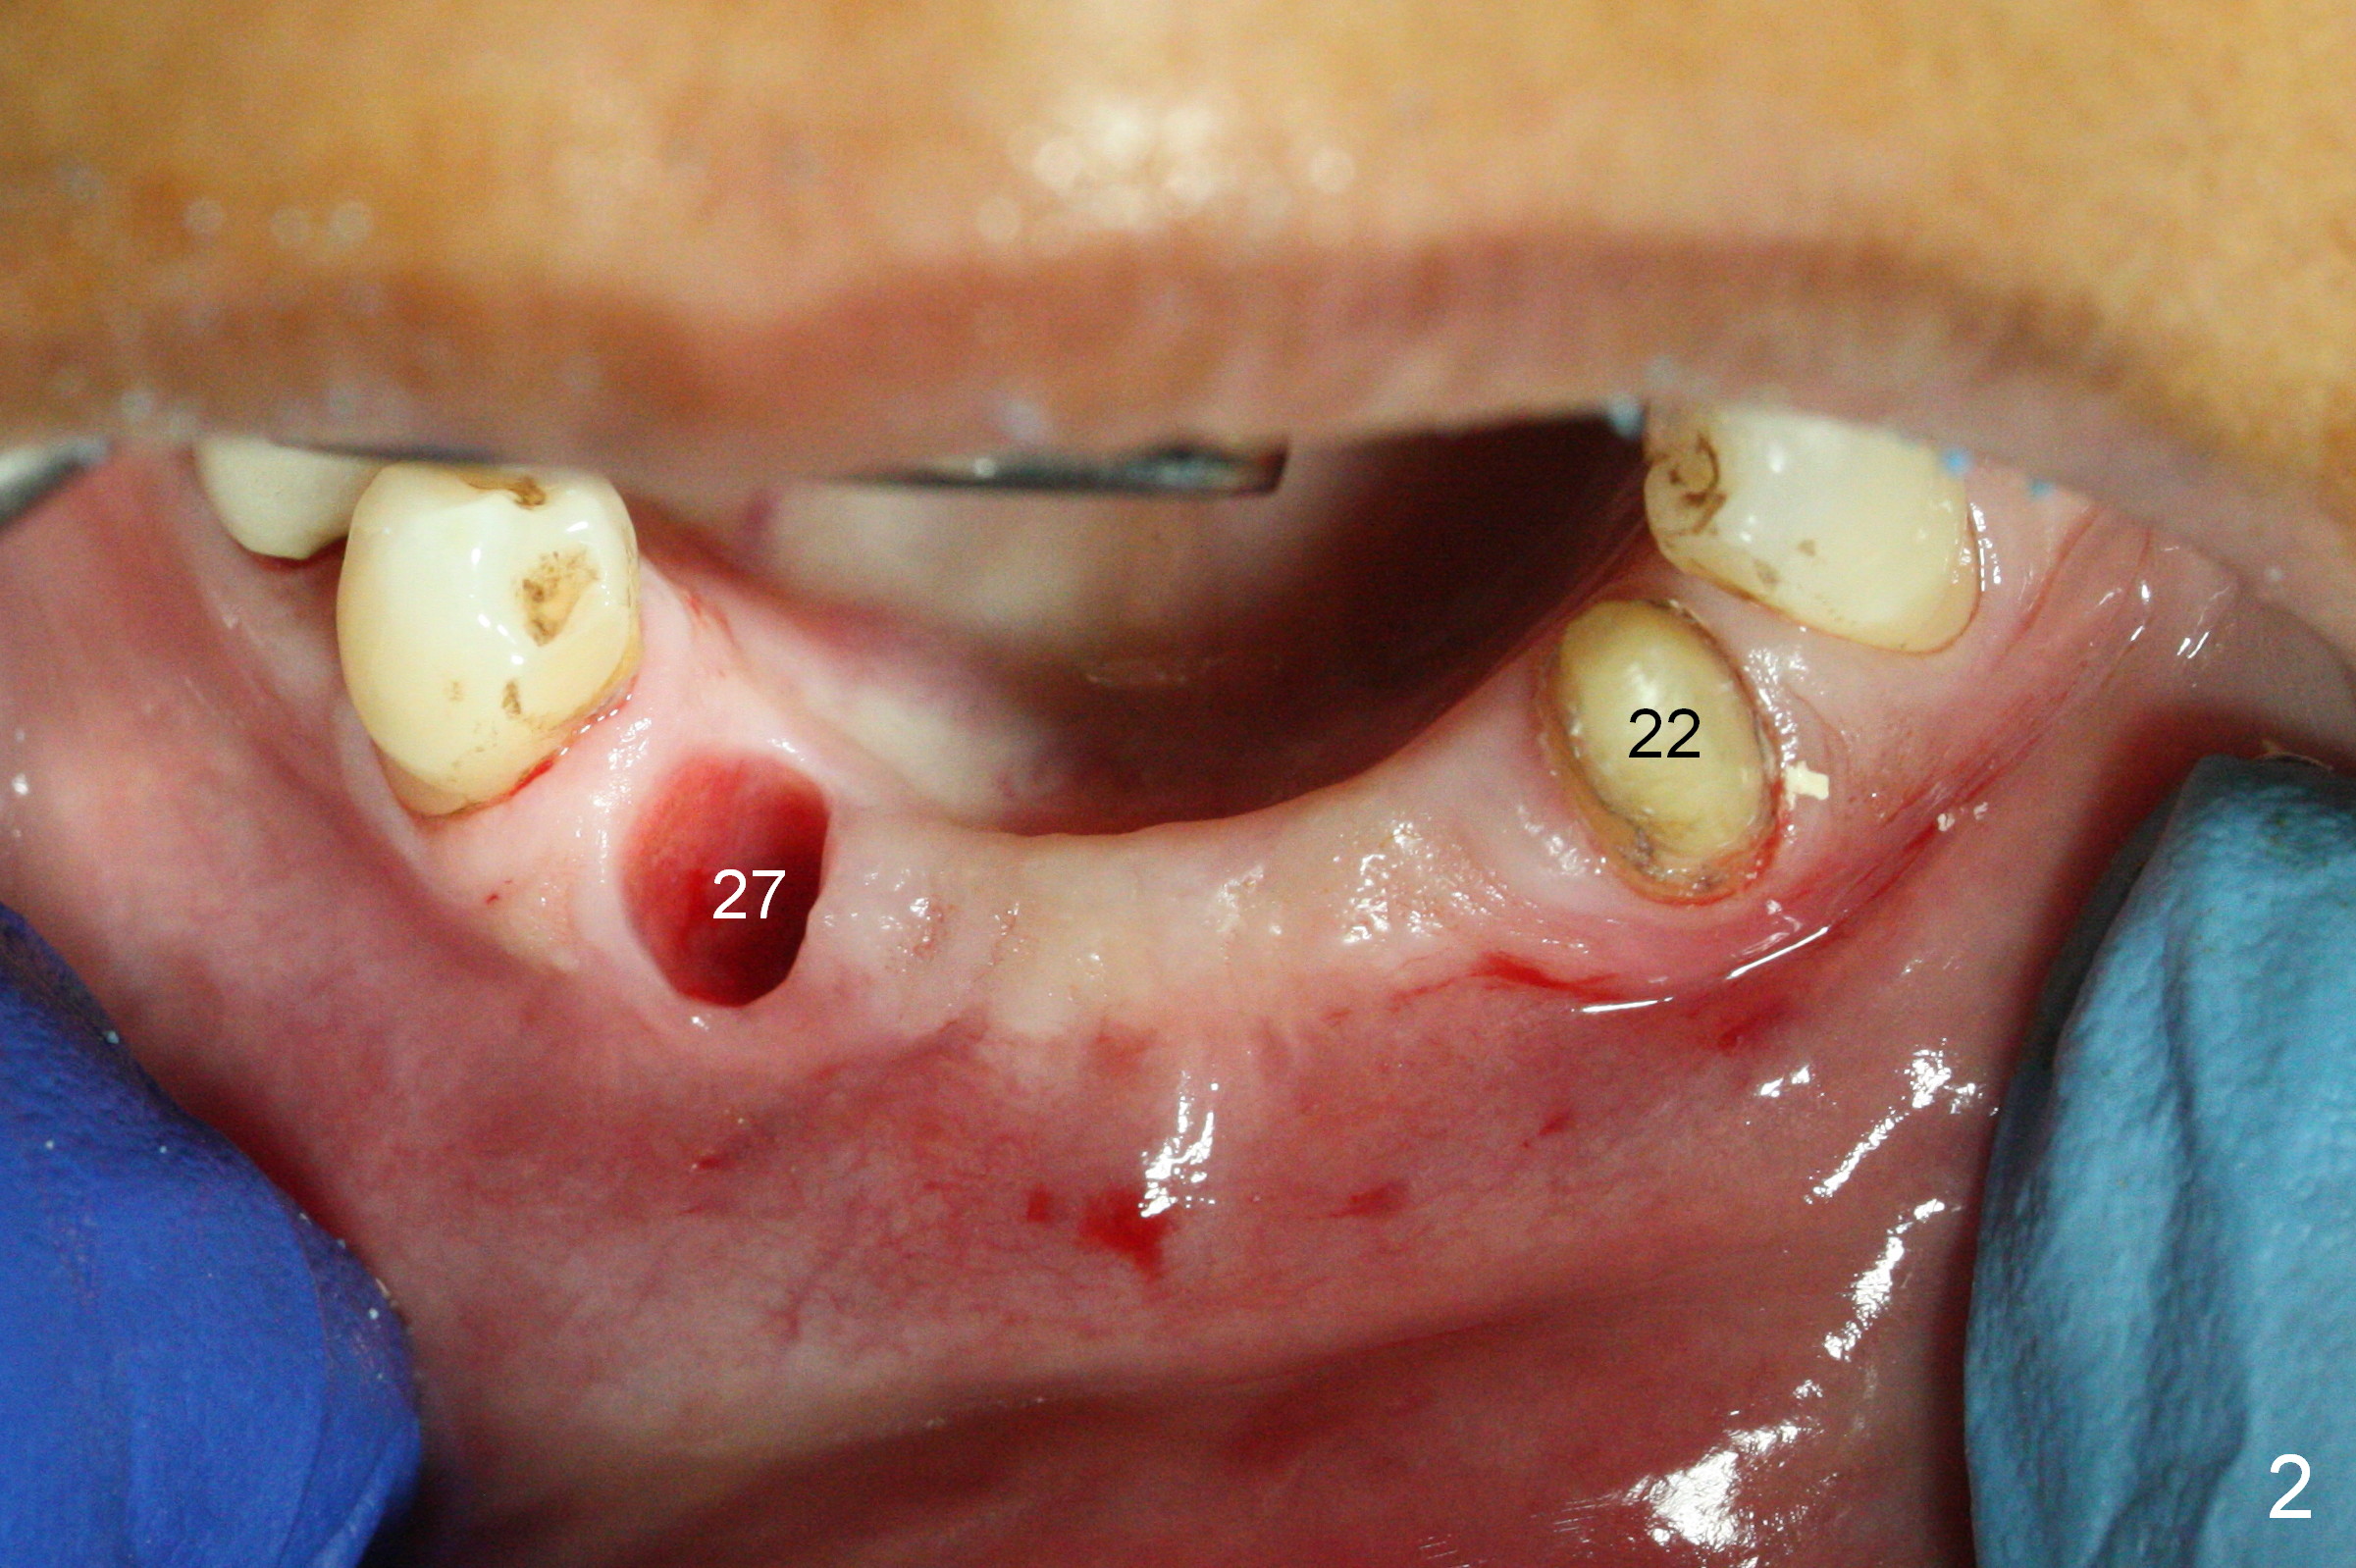

There is severe buccal gingival recession at #27 (Fig.1 arrow), as compared to that at #22. After removing the bridge and extraction of #27 (Fig.2 with severe loss of the buccal plate), a 3x18 mm drill is used to finish osteotomy (Fig.3). A 3.8x13 mm UF implant (Fig.3 green line) will be placed with 9 mm in the apparently solid, native (new) bone (blue line), while the coronal 5 mm will be occupied by the 5 mm cuff of a cemented abutment (pink line). The white dashed line is the gingival margin. The osteotomy is initiated as lingual as possible so that there will be at least 2 mm buccal gap when the narrow implant is placed. In spite of effort and precaution (guided surgery could control the trajetory), the coronal end of the implant tilts buccally so that a 4.5 mm 15 ° A 4 mm angled abutment is placed slightly subgingival (except buccal; Fig.5 A).

Since the ridge between the lower canines is atrophic (Fig.2), osteotomy starts at #23 and 25 after crestal reduction (Fig.4 arrowheads), Two of 2.5x12(4) mm 1-piece implants are placed (Fig.6). The implants at #23, 25 and 27 and the tooth #22 support an immediate provisional bridge (Fig.7).